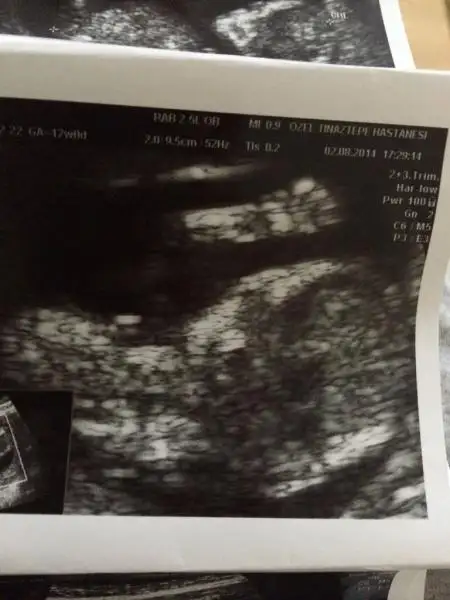

Kızımla biz allaha şükür iyiyiz resmi soran arkadaşlar vardı yüklüyorum maşallah giyin :)

Iki açıdanda fotosu var el sallıyor size

Saol canım inşallah görürsün sende eli kafasında yatıyo aynı bizim gibi eşimde bende öle yatarız mucize bu bence parmakları bile sayılıyo insanın inanası gelmiyor bazen Allah herkese yaşatsın bu duyguyu

14. Haftadayız canım büyüyoruz yavaş yavaş inşallah